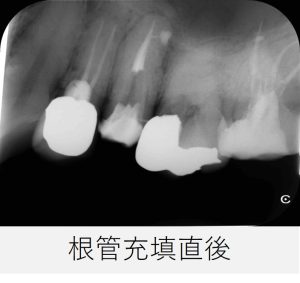

- その後、根管充填を行い、仮封しました。

- レントゲンを撮影し、根管充填の状態が良好であることを確認しました。